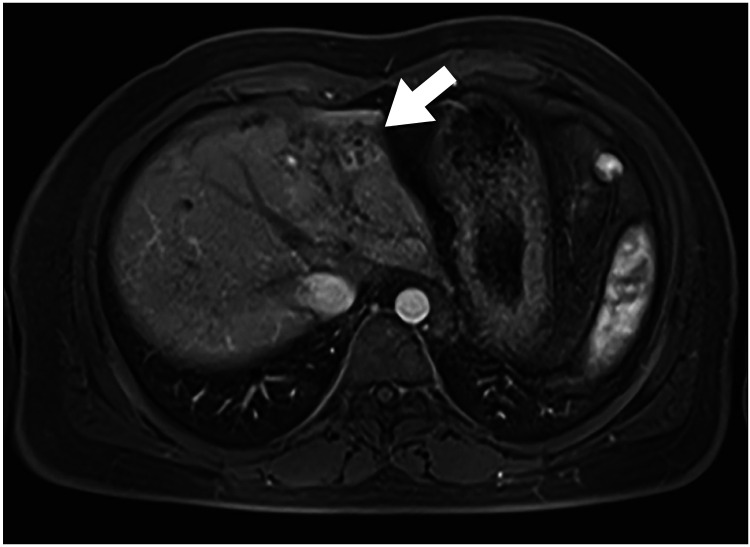

Results: An imaging study identified IBCs in 28 of 129 patients who underwent KPE with biliary atresia (21.7%). Among them, 5 patients were subjected to surgical treatment for intractable cholangitis. The median time from KPE to the development of IBCs was 1.7 years. Four out of 5 patients had IBCs confined to the left lateral lobe, and in one patient, the IBCs were in the hepatic hilum. All 5 patients experienced more than one cholangitis. Although they received intravenous antibiotic treatment and percutaneous transhepatic cholangiodrainage as treatment, they were intractable. Three patients underwent hepatectomy, and 2 underwent cystojejunostomy. There was no recurrence of cholangitis during the median follow-up period of 2.9 years.